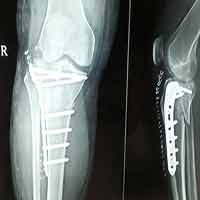

Case:14 Periprosthetic Fracture

60 years old patient with total knee replacement on left knee presented with open grade 1 injury. Debridement & slab given on emergency bases. Fixation with plate & screws done. Union was seen after 6 months.

Pre-Op AP

Pre-Op Lat.

Immdiate Post-op

1 and half months Post-op

2 and half months Post-op

3 and half months Post-op

4 and half months Lateral

6 Years Follow-Up